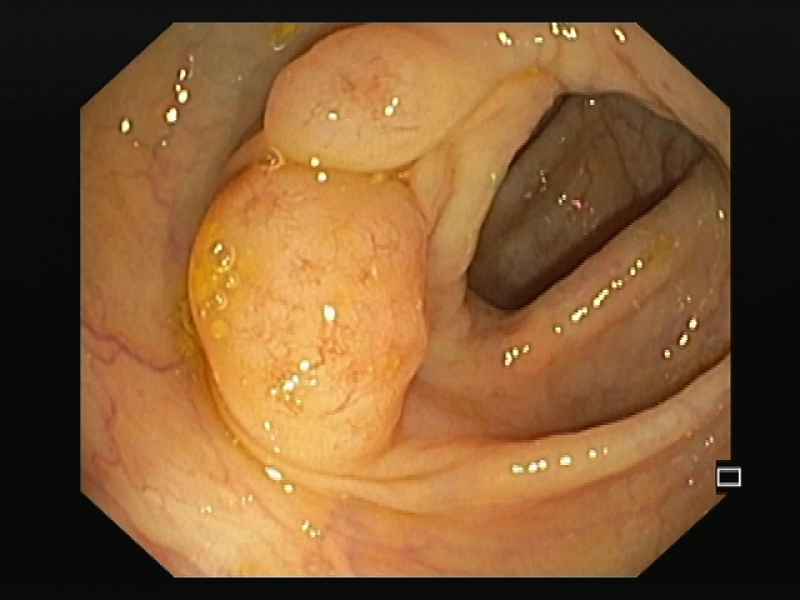

Cavernous hemangioma of the sigmoid colon : a rare cause of rectal bleeding

Fotografias